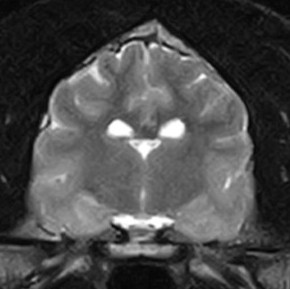

脳の異常を調べるため、MRI検査を実施

脳実質に炎症や腫瘍形成、梗塞所見などを疑う器質的変化は認められず、側脳室拡大など水頭症や脳圧亢進を疑う明らかな所見も認められなかった

中耳や内耳領域にも特異所見は認められず、よって脳内に明らかな異常が認められなかったため「特発性てんかん」と診断